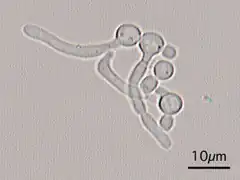

This "hyphal" denomination is due to Hwp1 appearing exclusively on the surface of a projection called hyphae that emerges from the surface of this fungus.

Candida Albicans Hyphal forms (filamentous projections called hyphaes emerging from round-to-oval forms)

Candida Albicans Hyphal forms (filamentous projections called hyphaes emerging from round-to-oval forms)